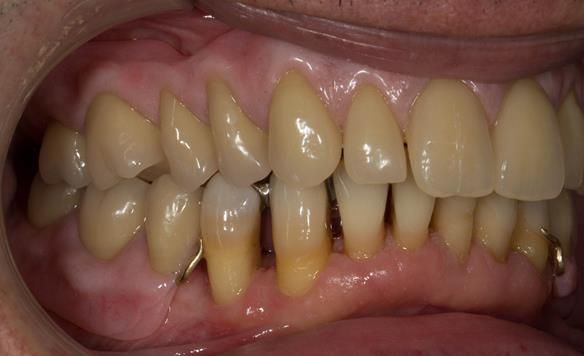

- Generalised periodontitis; stage IV grade C: currently unstable, risk factors: smoker.

- The remaining maxillary teeth had hopeless prognosis in the short term. They exhibited 80 - 100% alveolar bone loss with increased mobility (Grade 2 - 3).

- The lower right second premolar and lower left first premolar (LR5 LL4) had hopeless prognosis in the short term. They exhibited 80 - 100% alveolar bone loss with grade 3 mobility.

- The remaining mandibular teeth had approximately 30 - 50% alveolar bone loss with grade 1 mobility.

The clinical situation and treatment process is shown in detail below with photographs.